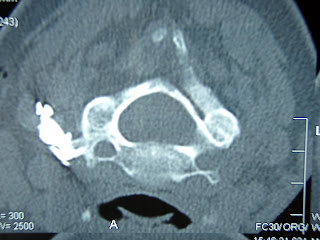

Five parallel lesions were performed around the valley of the upper part of the sacrum where the L5 posterior ramus runs. The image shows the needle in its most median position 1/3 up on the superior articular process of the sacrum. Compared to the two other levels, the needle pass was less cranial. The projection is oblique, parallel to the L4/5 disc.